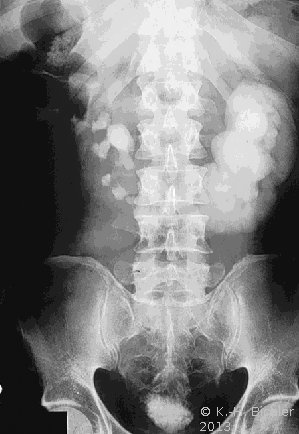

Im Ausscheidungsurogramm und im CT war eine Hufeisenniere mit Pyelektasie links zu erkennen (Abbildung 5).